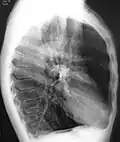

A chest X-ray is not useful to establish a diagnosis of COPD, but it is of use in either excluding other conditions or including comorbidities such as pulmonary fibrosis and bronchiectasis. Characteristic signs of COPD on X-ray include hyperinflation (shown by a flattened diaphragm and an increased retrosternal air space) and lung hyperlucency.[5] A saber-sheath trachea may also be shown that is indicative of COPD.[111]

Chest X-ray demonstrating severe COPD, displaying small heart size in comparison to the lungs

A lateral chest X-ray of a person with emphysema, displaying barrel chest and flat diaphragm